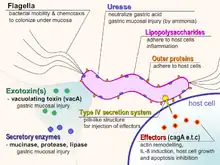

Helicobacter pylori harms the stomach and duodenal linings by several mechanisms. The ammonia produced to regulate pH is toxic to epithelial cells, as are biochemicals produced by H. pylori such as proteases, vacuolating cytotoxin A (VacA) (this damages epithelial cells, disrupts tight junctions and causes apoptosis), and certain phospholipases.[43] Cytotoxin associated gene CagA can also cause inflammation and is potentially a carcinogen.[44]

H. pylori is able to sense the less acidic pH gradient in the mucus, and using its flagella can move towards it. Once there it can burrow through into the underlying epithelial cell layer.[88] H. pylori is found in the mucus, on the inner surface of the epithelium, and occasionally inside the epithelial cells themselves.[89] H. pylori adheres to the epithelial cells by producing adhesins, known virulence factors, which bind to lipids and carbohydrates in the epithelial cell membrane. This keeps the bacteria from being swept away with the constant movement of the mucus from the lining to its dissolution into the stomach lumen.[90]

One such adhesin, BabA, binds to the Lewis b antigen displayed on the surface of stomach epithelial cells.[91] H. pylori adherence via BabA is acid sensitive and can be fully reversed by a decreased pH. It has been proposed that BabA's acid responsiveness enables adherence while also allowing an effective escape from unfavorable environment at pH that is harmful to the organism.[92] Another such adhesin, SabA, binds to increased levels of sialyl-Lewis X (sLeX) antigen expressed on gastric mucosa.[93]

In addition to using chemotaxis to avoid areas of low pH (high acidity), H. pylori also neutralizes the acid in its environment by producing large amounts of urease, an enzyme which breaks down the urea present in the stomach to carbon dioxide and ammonia. These react with the strong acids in the environment to produce a neutralized area around H. pylori.[94] Urease expression is not only required for establishing initial colonization but is essential for maintaining chronic infection.[60] Another enzyme Helicobacter pylori arginase is crucial for establishing infection in the stomach. Arginase is a bimetallic metalloenzyme that also provides acid resistance. Arginase also helps the pathogen evade the host’s immune system by competing with the host’s production of nitric oxide normally a major component of the innate immune system.[95]

Virulence factors

CagA (cytotoxin-associated gene A) codes for the major H. pylori virulence protein. Bacterial strains with the cagA gene are associated with the ability to cause ulcers, MALT lymphomas, and gastric cancer.[102][103] The cagA gene codes for a relatively long (1186-amino acid) protein. The cag pathogenicity island (PAI) has about 30 genes, part of which code for a complex type IV secretion system. The low GC-content of the cag PAI relative to the rest of the Helicobacter genome suggests the island was acquired by horizontal transfer from another bacterial species.[36] The serine protease HtrA also plays a major role in the pathogenesis of H. pylori. The HtrA protein enables the bacterium to transmigrate across the host cells' epithelium, and is also needed for the translocation of CagA.[104]

The vacA (Q48245) gene codes for another major H. pylori virulence protein. There are four main subtypes of vacA: s1/m1, s1/m2, s2/m1, and s2/m2. s1/m1 and s1/m2 subtypes are known to cause increased risk of gastric cancer.[105] This has been linked to the ability for toxigenic vacA to promote the generation of intracellular reservoirs of H. pylori via disruption of calcium channel TRPML1.[106]

The virulence of H. pylori may be increased by genes of the cag pathogenicity island; about 50–70% of H. pylori strains in Western countries carry it.[107] Western people infected with strains carrying the cag PAI have a stronger inflammatory response in the stomach and are at a greater risk of developing peptic ulcers or stomach cancer than those infected with strains lacking the island.[27] Following attachment of H. pylori to stomach epithelial cells, the type IV secretion system expressed by the cag PAI "injects" the inflammation-inducing agent, peptidoglycan, from their own cell walls into the epithelial cells. The injected peptidoglycan is recognized by the cytoplasmic pattern recognition receptor (immune sensor) Nod1, which then stimulates expression of cytokines that promote inflammation.[108]

The type-IV secretion apparatus also injects the cag PAI-encoded protein CagA into the stomach's epithelial cells, where it disrupts the cytoskeleton, adherence to adjacent cells, intracellular signaling, cell polarity, and other cellular activities.[109] Once inside the cell, the CagA protein is phosphorylated on tyrosine residues by a host cell membrane-associated tyrosine kinase (TK). CagA then allosterically activates protein tyrosine phosphatase/protooncogene Shp2.[110] Pathogenic strains of H. pylori have been shown to activate the epidermal growth factor receptor (EGFR), a membrane protein with a TK domain. Activation of the EGFR by H. pylori is associated with altered signal transduction and gene expression in host epithelial cells that may contribute to pathogenesis. A C-terminal region of the CagA protein (amino acids 873–1002) has also been suggested to be able to regulate host cell gene transcription, independent of protein tyrosine phosphorylation.[103] A great deal of diversity exists between strains of H. pylori, and the strain that infects a person can predict the outcome.